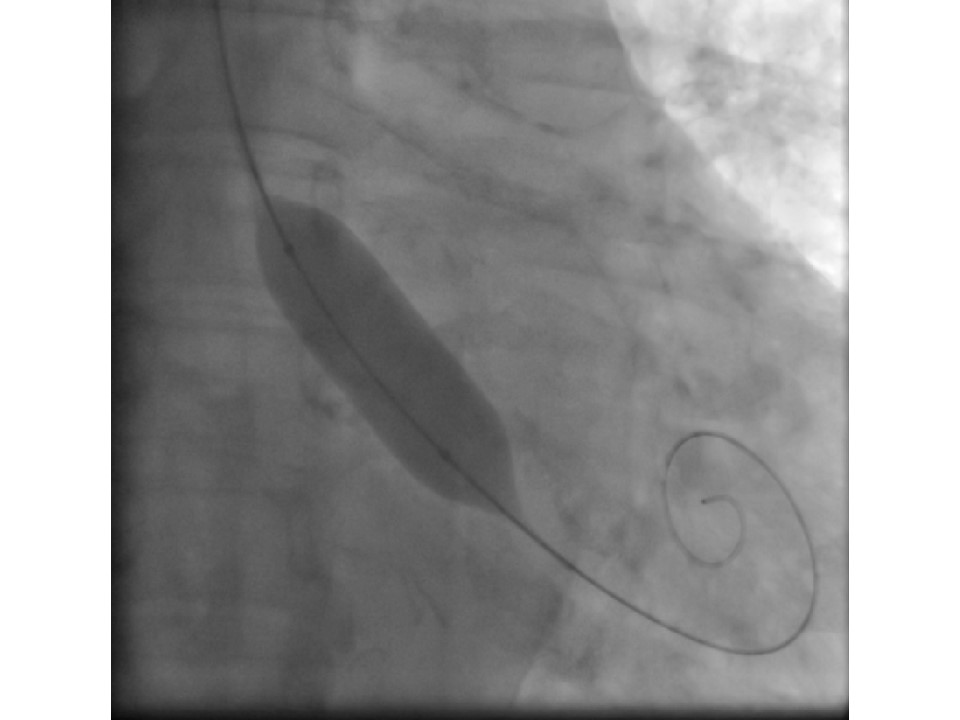

Single-access sheathless #RadialFirst 18mm Balloon Aortic Valvuloplasty. A few years ago it was 12F & 6F bifemoral artery + 7F femoral vein. @shci_sec @PCRonline #cardiotwitter